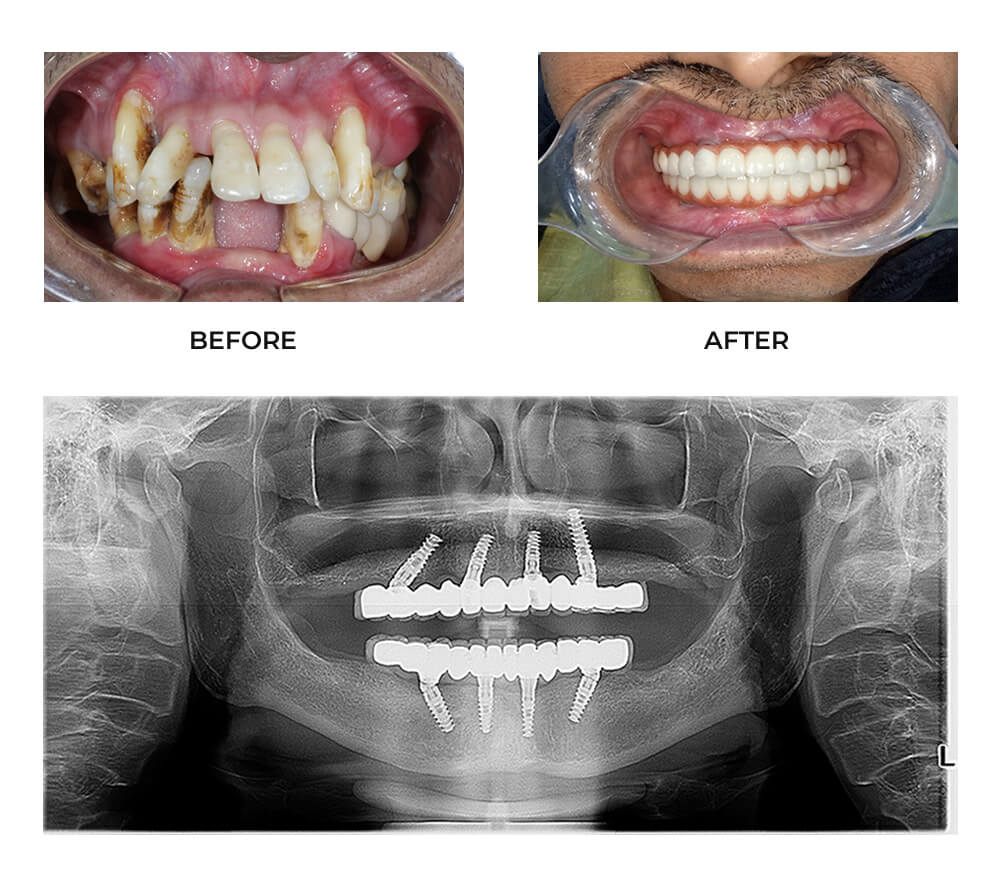

All-on-4 Dental Implants in Hyderabad offer an innovative and permanent solution for people who have lost most or all of their teeth. With this advanced dental technique, you can replace your missing teeth in just one visit, restoring not only your smile but also your confidence and ability to eat comfortably. This treatment is especially popular among people seeking immediate, long-lasting teeth replacement without undergoing multiple surgeries or long waiting times.

Many people avoid dental implants due to the fear of multiple appointments and long treatment durations. However, with All-on-4 Dental Implants in Hyderabad, you can now get permanent teeth in a single visit. Clinics like Dermadent Dental Clinic use advanced digital scanning and surgical guides to perform same-day implant placement and teeth restoration with minimal discomfort. This “teeth in a day” concept is ideal for people who want to restore full function and aesthetics immediately, especially those who have an upcoming event or professional commitments.

Your dentist performs a thorough examination using digital X-rays and 3D scans to assess your bone condition and plan implant placement accurately.